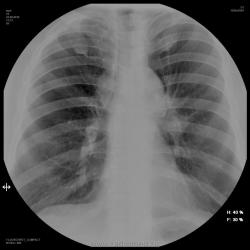

Мужчина 70 лет, поступил в пульмонологическое отделение

Всем здравствуйте! Мужчина 70 лет поступил в пульмонологическое отделение с диагнозом хронический обструктивный бронхит. Редкий кашель .Слабость. Ночной пот. Синкопальные состояния.

БЫЛО БЫ ПРОЩЕ , ЕСЛИ БЫ СРЕДОСТЕНИЕ БЫЛО СПОКОЙНОЕ... ВЫСТАВИЛ ДИФ РЯД. - ТБС ВНУТРИГРУДНЫХ ЛУ С ПОРАЖЕНИЕМ ЛЕГКИХ И ПЕРИФЕРИЧЕСКИЙ РАК С МТС В ЛУ СРЕДОСТЕНИЯ . БОЛЬШЕ ВРОДЕ В ГОЛОВУ НИЧЕГО НЕ ПРИХОДИТ... БЫЛ БЫ РАД МНЕНИЯМ КОЛЕГ ПО ВЫСТАВЛЕННОМУ - ЗА И ПРОТИВ. А МОЖЕТ ЕЩЕ КТО ЧТО ПОДСКАЖЕТ.

"Архивчик", конечно есть, и не только в виде "кальцинатов", но как- то больше склоняюсь к "мета" в узлы средостения. Эта "скромница" слева на верхушке вполне может быть "первичкой".

Конечно, такую картинку может дать, и "мягкотелая" туберкулома, вроде-бы, как и архив есть, но чем не периферический или метастаз, да и "дорожка" не тубарская, а еще и "лучистость" из корня.

Да, и это "томки" на тубарь не воодушевили, может уже "МЕТА"?.

Да, и позвонки неоднозначные, хотя, и похожи по теневой картине на гемангиому. Нет, я за "Мета".

Периферический рак S1-2 слева с метастазами в  бронхопульмональные лимфоузлы  слева, перитрахеальные с обеих сторон и парааортальные л.у.